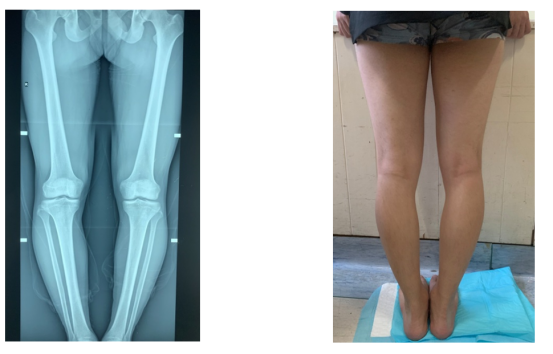

年仅20岁的王先生,本应是在朝气蓬勃的年纪里享受着美好的青春,却因双膝关节内翻畸形而困扰多年。患病期间,王先生常因双膝内翻畸形感到自卑,当看到同龄人参加各类运动项目、体育活动等,甚是羡慕。

经过全面检查及系统评估,孙宝玲主任带领的关节外科团队建议王先生进行胫骨高位截骨术(HTO)。王先生和家人在详细了解胫骨高位截骨术(HTO)后决定进行手术。

△术前

经过关节外科团队严谨的术前准备后,于术中确认合适的截骨平面,C型臂下透视测量下肢外观恢复变直,确保受力均匀,安放接骨板,反复确认力线......经过2个多小时的努力,顺利完成手术。

王先生术后恢复良好,经过科学的术后护理及康复训练已经顺利出院。

△术前、术后对比